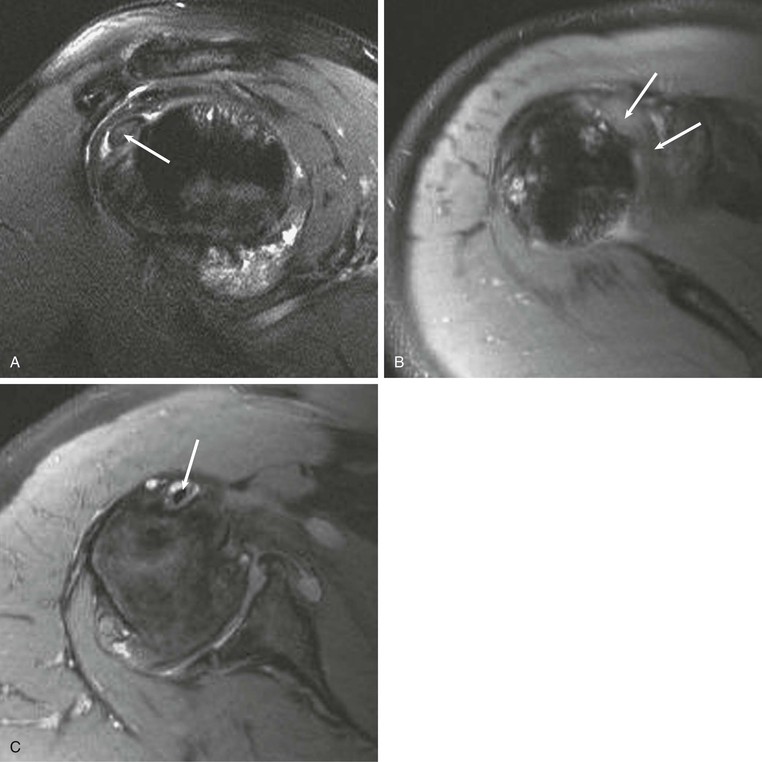

Most cuff tears originate in the supraspinatus tendon; however, large tears may extend into either the infraspinatus or subscapularis tendon. Isolated tears, although less common, occasionally occur in either the infraspinatus or subscapularis (Fig. 44-24) tendon. An isolated tear of the infraspinatus tendon is usually associated with the internal impingement syndrome (discussed further in the section on glenohumeral instability).104 An isolated tear of the subscapularis tendon may result from shoulder dislocation or in association with coracohumeral impingement112 and is best demonstrated on axial MRI as high signal traversing the tendon with retraction of the tendon away from its normal attachment site on the lesser tuberosity. An extension of the subscapularis tendon known as the transverse ligament holds the long head of the biceps tendon in the intertubercular groove, and a tear of the subscapularis tendon may result in disruption of the transverse ligament, leading to medial subluxation or dislocation of the long head of the biceps tendon.113 Axial MRI is well suited not only for evaluating the integrity of the subscapularis tendon but also for demonstrating medial subluxation of the biceps tendon out of the intertubercular groove. The biceps tendon may be displaced superficial to the subscapularis tendon, into the subscapularis tendon (Fig. 44-25) or intraarticular (Fig. 44-26).

Subluxation or dislocation of the tendon out of the intertubercular sulcus can result from injury to the overlying stabilizing structures.113 A tear of the coracohumeral ligament will result in medial subluxation of the long bicipital tendon, and three patterns of subluxation have been described that are related to the status of the subscapularis tendon and the coracohumeral ligament (Table 44-4). First, disruption of the coracohumeral ligament in conjunction with a complete tear or avulsion of the subscapularis tendon off of the lesser tuberosity will result in an intraarticular subluxation or dislocation. The long bicipital tendon will sublux medially into the anterior aspect of the glenohumeral joint, medial to the intertubercular groove. Second, a tear of the coracohumeral ligament in conjunction with a tear of the transverse humeral ligament (superficial fibers of the subscapularis tendon) will result in extraarticular subluxation of the long bicipital tendon, and the tendon will be located medial to the intertubercular groove but superficial to the intact fibers of the subscapularis tendon. Finally, an isolated tear of the coracohumeral ligament with an intact subscapularis tendon and transverse humeral ligament will allow medial migration of the long bicipital tendon into the substance of the subscapularis tendon, resulting in interstitial tearing of the tendon. This lesion is the so-called hidden lesion because the abnormal position of the tendon may not be visible to the arthroscopist. Preoperative MRI can alert the surgeon to the abnormal position of the long bicipital tendon because axial MRI nicely depicts the location of the long bicipital tendon medial to the intertubercular groove (see Fig. 44-26).